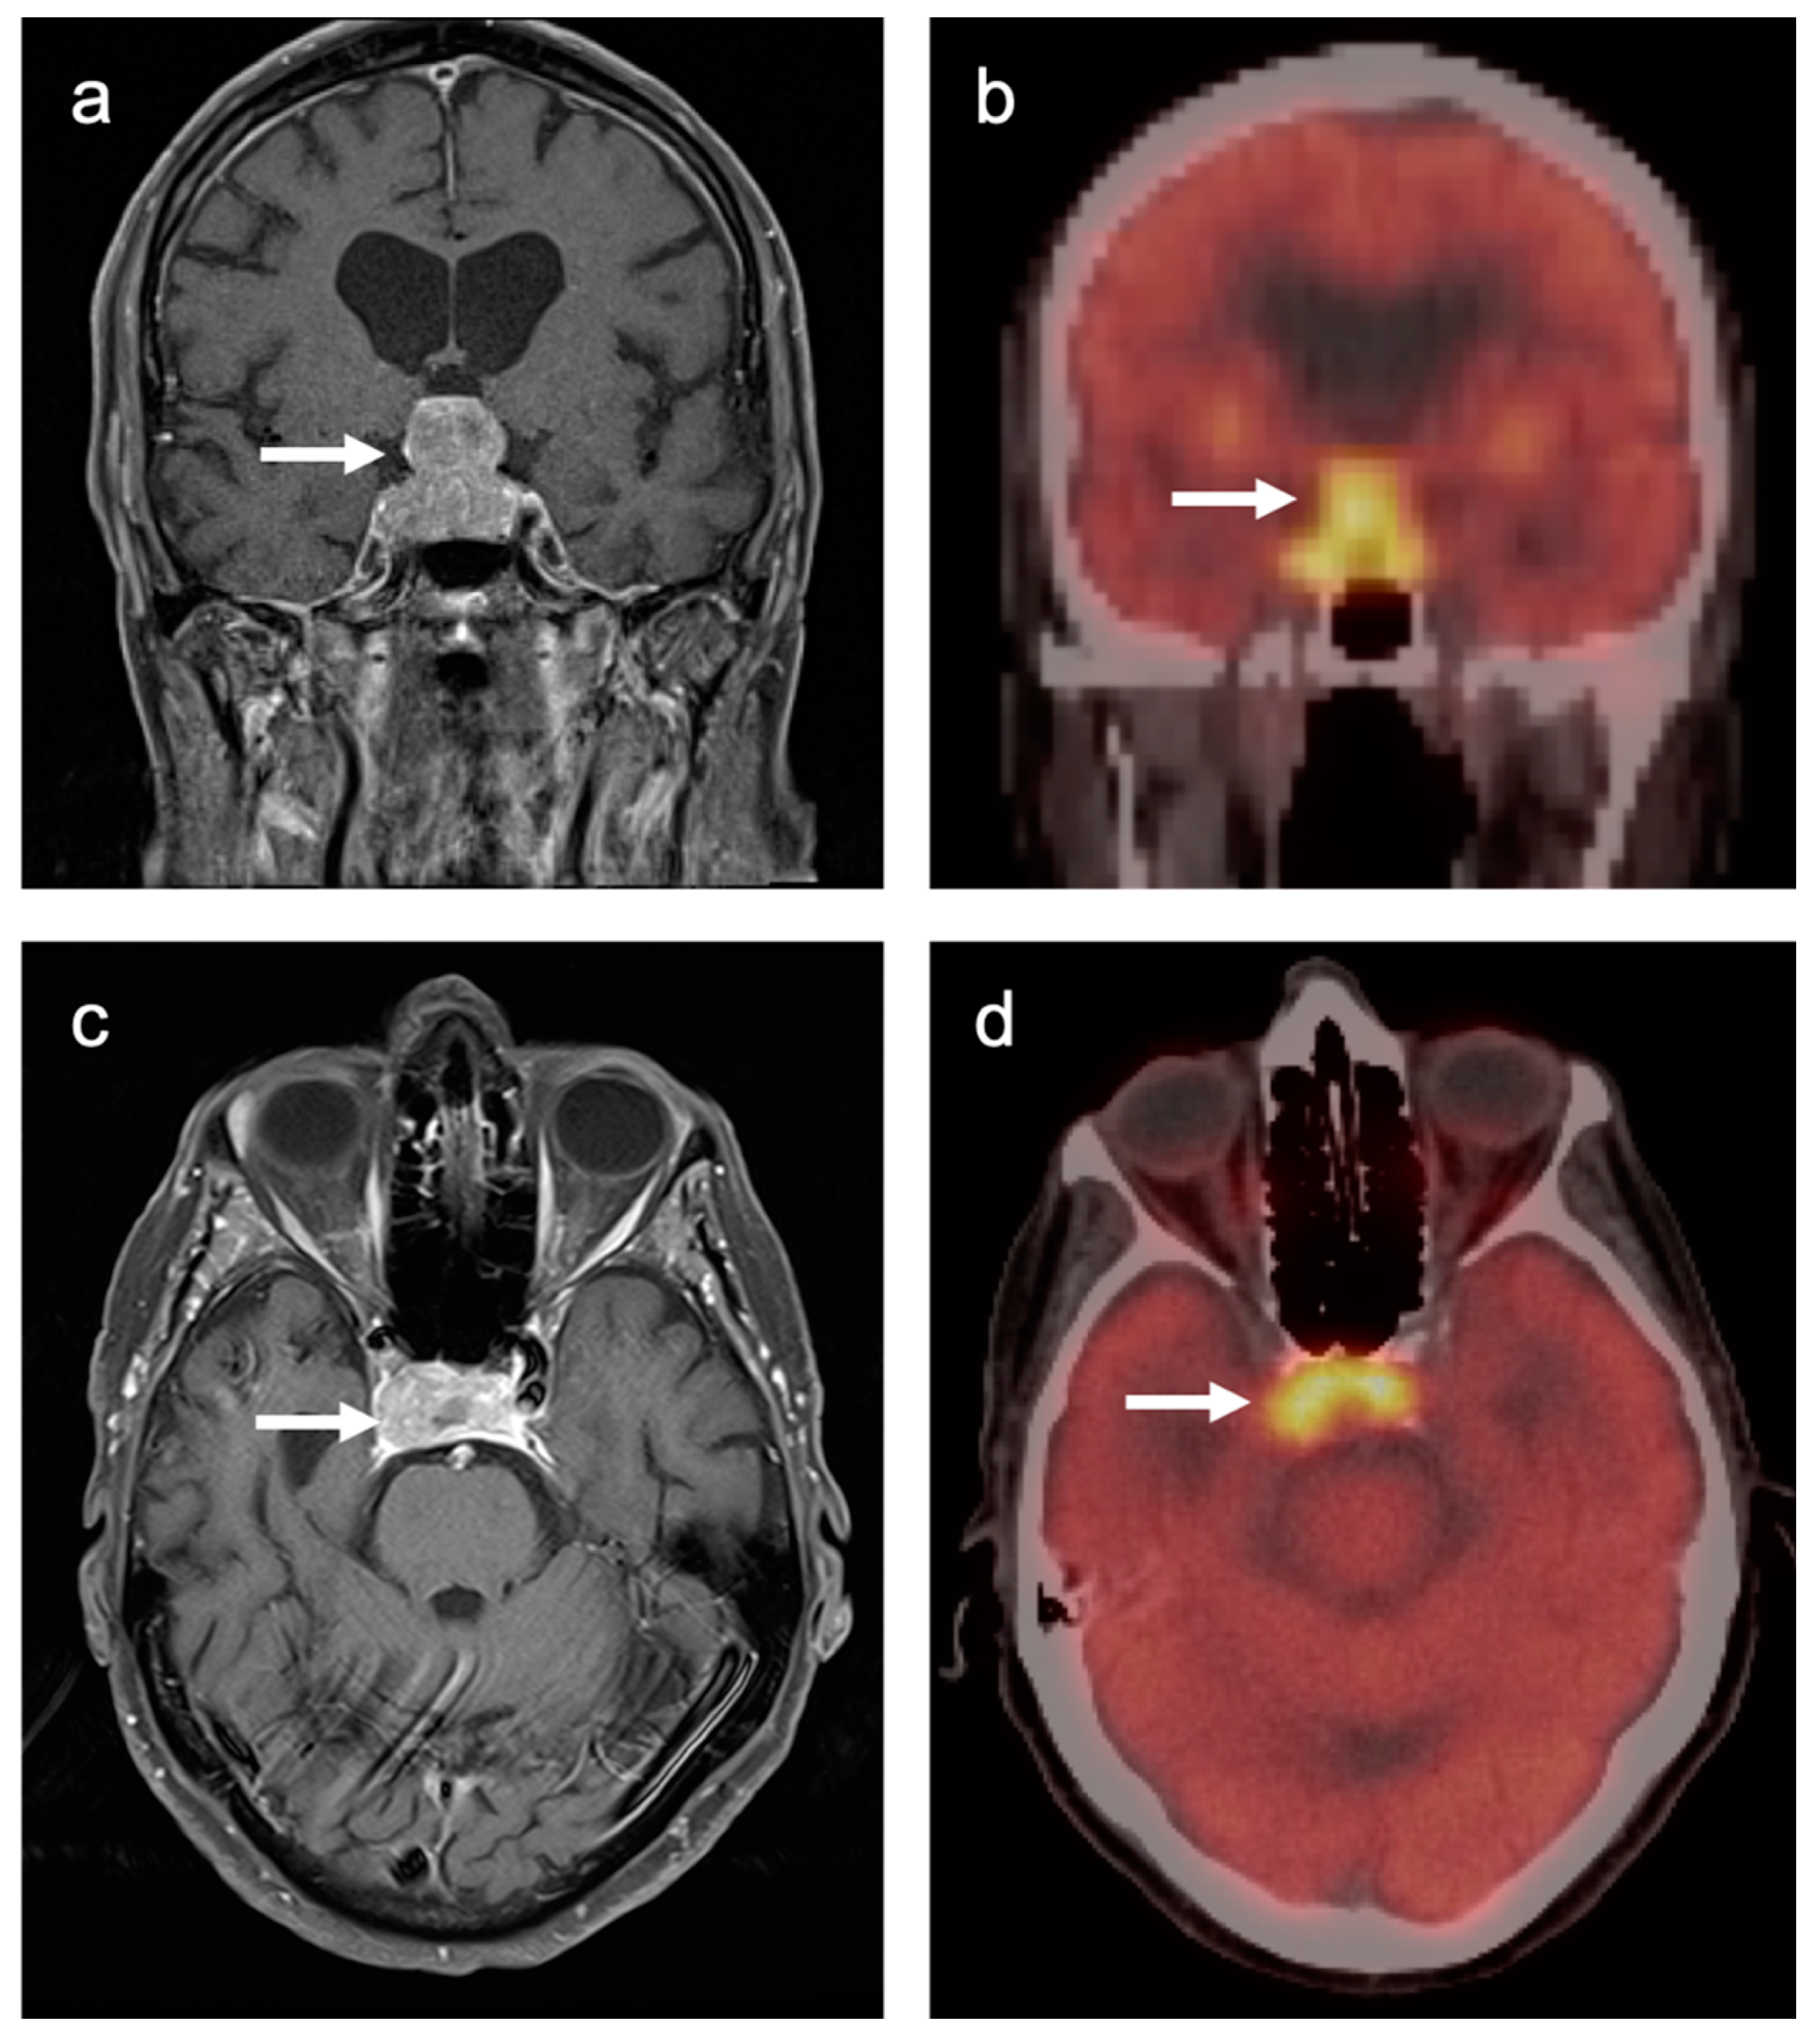

3.4. CNS Lymphoma

3.7. Meningioma